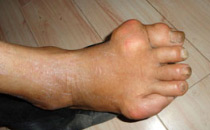

跗跖关节

例子

病症描述:跗跖关节痛风急性发作期,跗跖关节明显肿胀、发红、压痛明显、功能障碍。

在线客服医院电话

(注:如出现以上症状请及时在线导诊或者到院就医。)